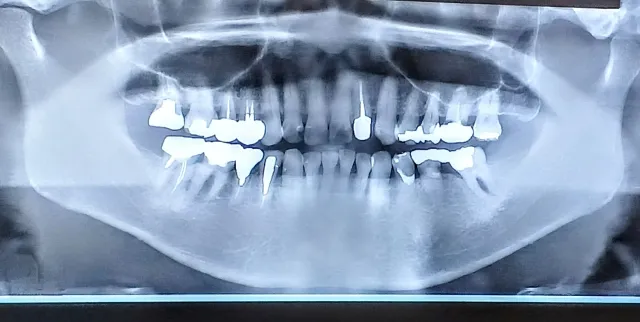

①レントゲンを撮影・治療スケジュールをお伝えします。

必要に応じレントゲンを撮影した後に、どの歯から治療していくか決めます。

基本的には痛みが出ている歯・早急に治療が必要な歯から治療を始めます。

1回や2回では終わりませんので、ある程度長期に渡って少しずつ治療を進めていきます。